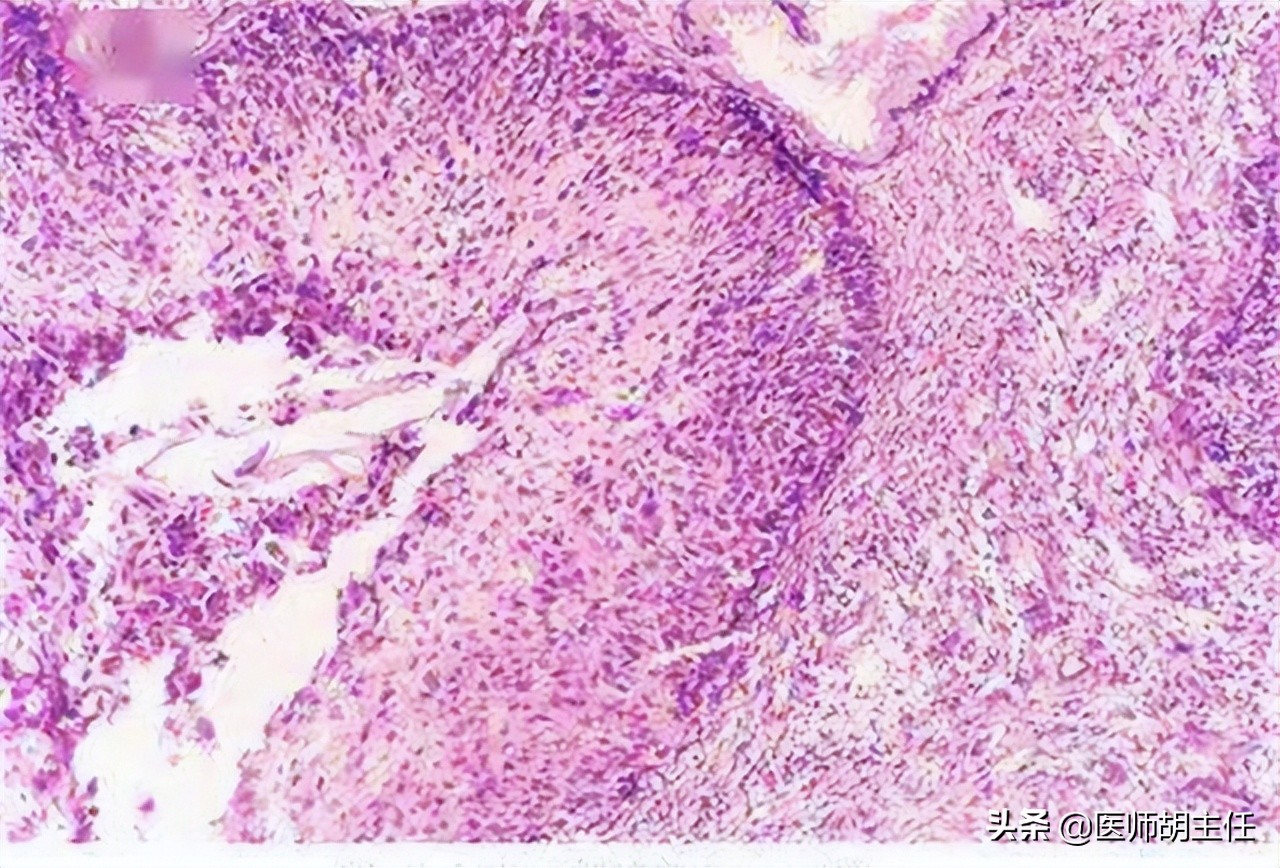

双附件:双附件未扪及明显包块。外院HPV基因型检测提示: 高危型HPV:阳性(16) ; 阴道镜检查活检回报:宫颈浸润癌,确诊为宫颈癌。

子宫颈癌是人体子宫颈部上皮细胞上的基因发生了突变导致 异常增殖而形成的新生物 。

在SIL这个时期,可以自然消退,但如果我们没有及时发现它也可以发展为子宫颈癌。肿瘤根据影响的大小也可以分为良性肿瘤和恶性肿瘤。癌其实是上皮组织发展过来的一种恶性肿瘤, 子宫颈癌就是一种子宫颈部的恶性肿瘤 。